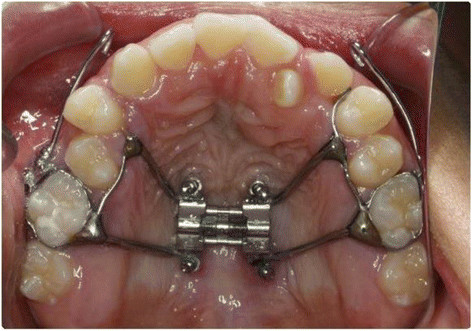

Oral Protraction Head Gear, Palatal Expanders, Protraction Facemasks,

Reverse Pull Headgear, Orthodontic Facemasks

Micro-implant-supported hyrax with facemask

Source: Research Gate